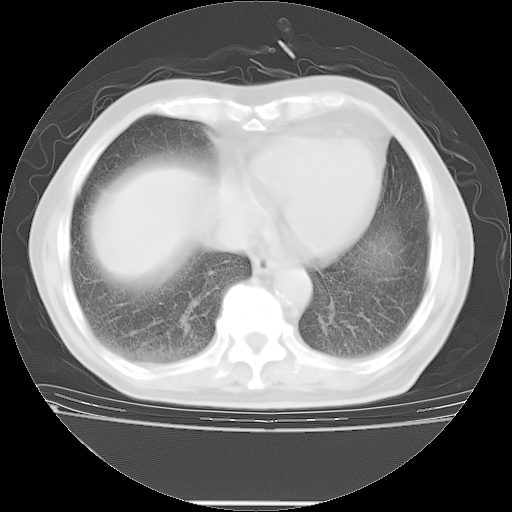

今天复查肺部CT,发现双肺广泛磨玻璃样改变。所以我把3月19日和5月9日相隔50天的肺部CT上传。请大家会诊。

5月9日肺部CT(在4月27日齐鲁医院肺部CT描述部分肺组织磨玻璃样改变,12天后肺组织广泛磨玻璃样改变)

2009年5月9日肺部CT